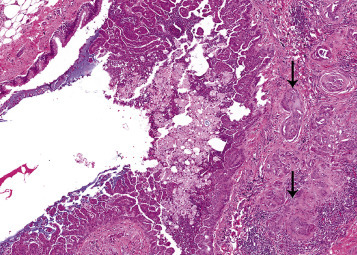

Fibrosis of the pleura or alveolar parenchyma including the bronchioles is an infrequent spontaneous finding in laboratory rats (Figure 23.10 ), but in these sites, is a common response to repeated or chronic injury resulting from infectious disease, systemic administration of chemicals, or inhalation of irritant chemicals. However, severe acute lung injury from a single exposure to highly irritant chemicals may induce a rapid fibrogenic response that may or may not be reversible (Renne et al., 2009). Critical to the development of fibrosis is the release of fibrogenic cytokines and fibronectin from pulmonary macrophages activated during the inflammatory response. Fibroblasts migrate into the fibrin casts and produce collagen. Depending on the extent and severity of injury, fibrosis may resolve slowly or may not completely resolve. Chronic exposure of rats to 2,3-butanedione (Morgan et al., 2016), cobalt sulfate heptahydrate (Bucher, 1991), indium phosphide (NTP, 2001), nickel sulfate hexahydrate (NTP, 1996b), and ozone (NTP, 1994) by inhalation has been reported to induce fibrosis.

Figure 23.10.

Pleural fibrosis (arrows) adjacent to an area of subpleural chronic inflammation in the lung of rat exposed to particulate by inflammation. Note fibrous thickening of the alveolar interstitium within the area of inflammation.